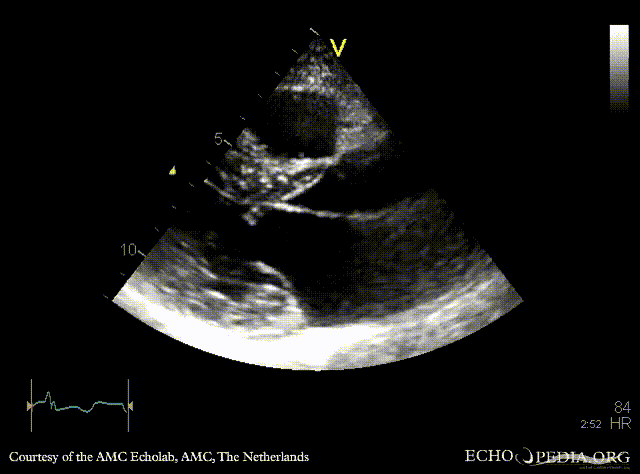

E00504.gif E00505.gif

A4CH: concentric hypertrophy of left ventricle, SAM of AMVL A3CH